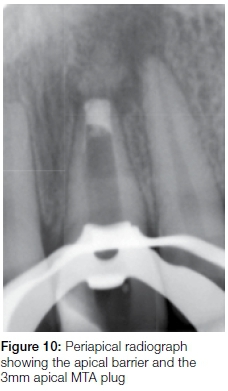

At the second visit, two weeks later, the medicament was removed by activating 3.5 % sodium hypochlorite with an Endo-Activator (Dentsply Sirona). Excess fluids were removed from the root canal using ISO size 100 paper points under DOM magnification. A mixture of DFDBA (Osseograft TM, Advanced Biotech Products) (Figure 4) and sterile water was prepared at the chairside. The mixture was placed in the coronal portion of the root canal and then manipulated apically and beyond the apex with the Machtou pluggers under the DOM, until resistance was felt at the point of the predetermined working length. White MTA (Dentsply Sirona) was then mixed according to the manufacturer's instructions and dispensed into the canal with the use of the Micro-Apical Placement System (MAP) system (Dentsply Maillefer). The dispensed MTA was moved apically against the apical matrix using the Machtou pluggers. A plug of approximately 3mm was created against the matrix in the apical part of the root canal and placement was checked radiographically (Figure 10). Another 2mm of additional MTA was packed in to create a 5mm apical plug before the canal was obturated with Pulp Canal Sealer (Kerr Corporation, Orange, Ca, USA) and warm gutta-percha dispensed from an Obtura II unit (Obtura Spartan, IL, USA)(Figure 11).